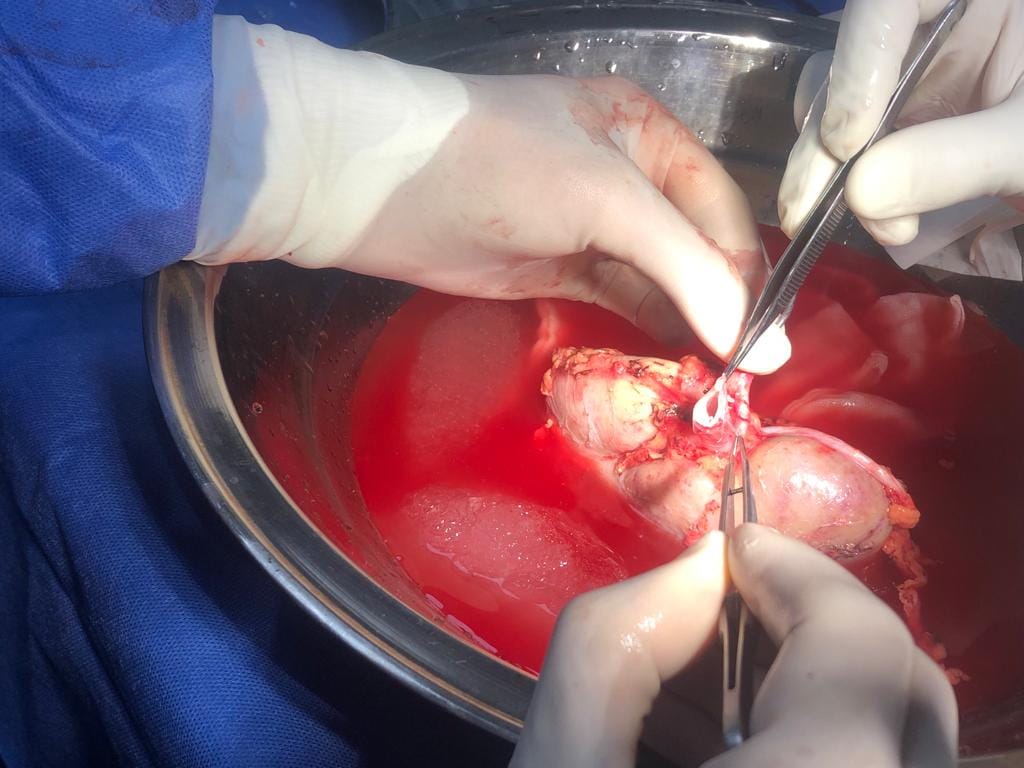

وكشف الدكتور هشام مختار حمودة مدير وحدة زراعة الكلى أن الحالة رقم 48 كانت زراعة كلى لشاب يبلغ من العمر 23 عام وبتبرع من والده الذى يبلغ من العمر 45 عام، والتى كانت عملية حرجة ومعقدة لوجود جلطة متكلسة بأوردة الطرف السفلى الأيمن ممتدة إلى الوريد الاجوف السفلى حتى مستوى قريب من الكليتين الأصليتين وهى ما تعتبر أحدى الحالات النادرة جداً وتمثل تحدياً للفريق الطبي الجراحي .

مضيفاً أن الحالة رقم ٤٩ تمت لشاب عمره ٢٣ سنة أيضا وكانت المتبرعة أخت المريض ذات ٢٢ عاما وكانت هذه الحالة تحدياً خاصاً حيث كان المريض لديه نسبة أجسام مضادة اعلي من المعتاد قبل العملية وهو ما يجعله أكثر عرضة لرفض الكلية المزروعة مما يمثل صعوبة تهدد نجاح الجراحة مما استدعى إعطاء ادوية مثبطة للمناعة خاصة وقوية قبل وأثناء وبعد العملية وتم وبفضل الله التعامل مع الحالة بمهنية وسياسة علمية صحيحة وبإرادة قوية من الفريق للنجاح وحرصهم على توفير الرعاية الصحية السليمة لهذا المريض.

وكشف الدكتور هشام حمودة عن خروج المرضى من المستشفى بوظائف كلى طبيعية ، متوجهاً بشكره إلى كافة أعضاء الفريق الطبي من أساتذة وأطباء متخصصين فى مجالات جراحة المسالك البولية والتخدير والباطنة وبتعاون أطباء الأشعة والباثولوجيا الإكلينيكية والصيدلة الإكلينيكية وفريق التمريض .